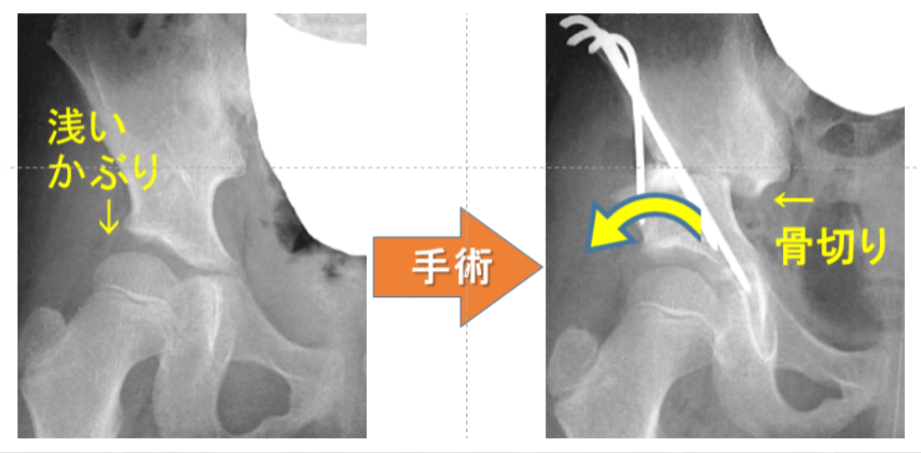

後遺症について

股関節脱臼が無事整復されたのちは、股関節の成長を定期的なX線検査などで見守りますが、股関節のかぶりが浅い「寛骨臼形成不全(臼蓋形成不全)」という後遺症がひどい場合、骨盤補正手術(骨盤骨切り術)を行います。できれば就学前に大きな治療を終わらせておく治療方針となります